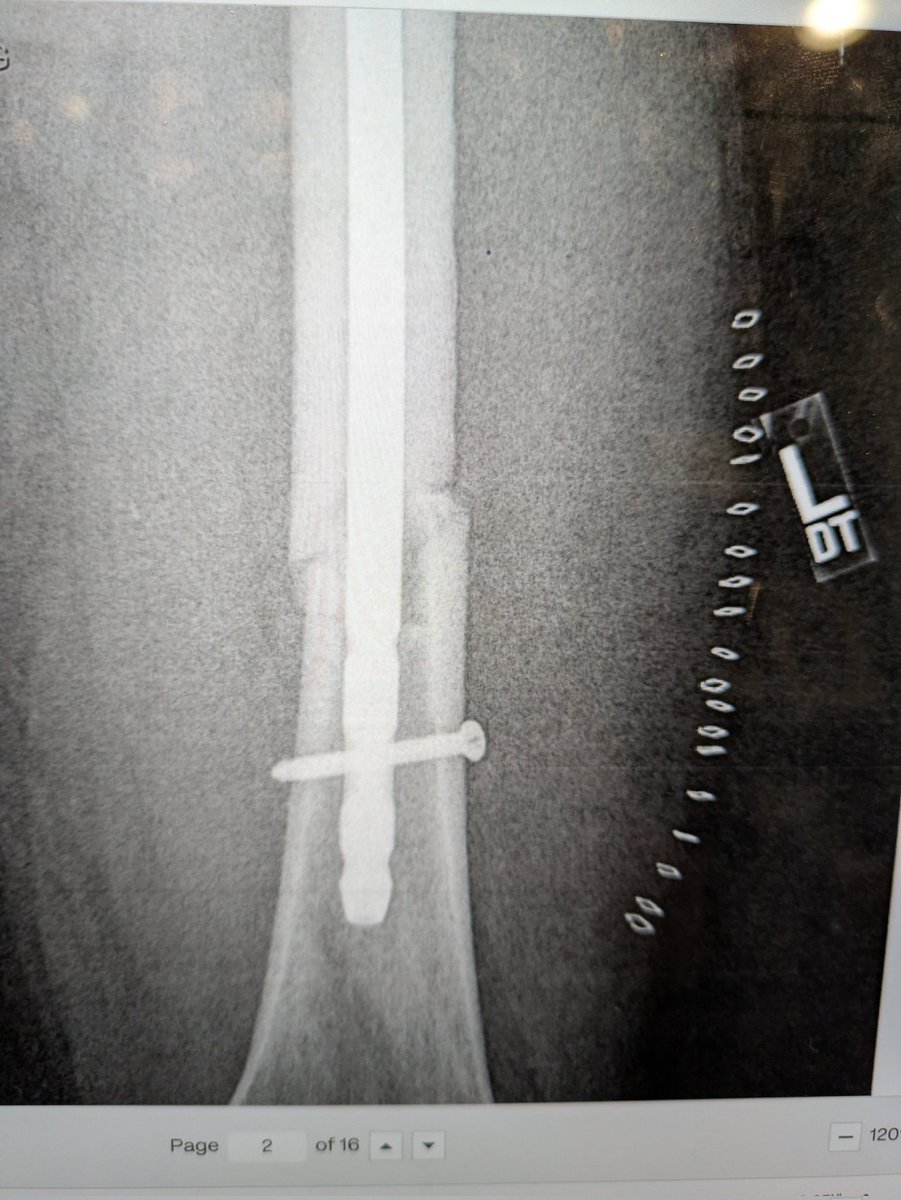

I’m bionic for real now 🦾